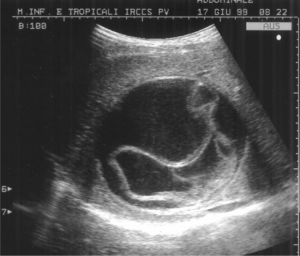

Accade molto frequentemente però che la presenza della tenia sia totalmente priva di sintomi, e che l’infezione venga rilevata solo dalla casuale visione di vermi vivi nelle feci. Le gravi complicazioni dovute alla presenza della tenia sono molto rare, e riguardano il blocco dei movimenti intestinali, oltre alla migrazione delle larve in altre parti dell’organismo, causando seri danni al fegato, agli occhi, al cuore e al cervello: in queste situazioni l’infezione si aggrava notevolmente, e può divenire addirittura letale.

L’infezione invasiva della tenia provoca la formazione di cisti negli organi compromessi, con relativi sintomi anche di grave entità e sovrainfezioni batteriche, febbre anche molto alta, e reazioni allergiche, compresa l’anafilassi.